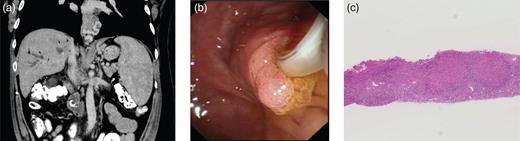

A 49-year-old male with no alcohol history presented to Glasgow Royal Infirmary with a 3-month history of right upper quadrant pain, jaundice, fever and 15 kg weight loss. Abdominal examination revealed hepatosplenomegaly, confirmed by abdominal ultrasound along with intrahepatic biliary tree dilatation. Liver function analysis revealed a mildly elevated bilirubin of 2.05 mg/dl. Computed tomography (CT) imaging demonstrated abrupt distal common bile duct (CBD) narrowing yet normal pancreatic duct. Notably, significant portal hypertension was evident with large para-esophageal varices and splenomegaly (Fig. 1a). With no obvious risk factors for chronic liver disease apart from obesity, alcoholic steatohepatitis was suspected. While magnetic resonance cholangiopancreatography was planned, cholangitis developed, prompting an ERCP, which revealed Grade B esophageal varices, an edematous ampulla (Fig. 1b) and a distal CBD filling defect, which was biopsied, with biliary drainage achieved using a plastic double pigtail stent. Histopathological examination revealed high-grade dysplasia within the bile duct adenoma. With potential for malignant progression, surgical resection was considered; however, comorbidity including obesity and sleep apnea compounded by portosystemic hypertension created a management dilemma.

(a) Preoperative CT scan revealed significant portal hypertension with large para-esophageal varices and splenomegaly. (b) ERCP image demonstrating the ampullary adenoma. (c) Liver biopsy reveals features in keeping with CHF.